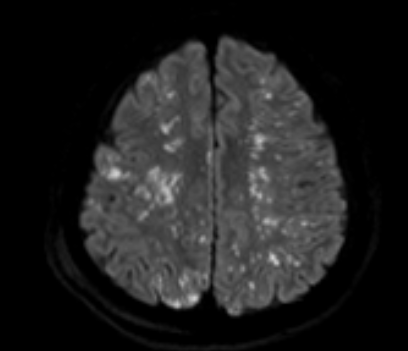

1) Starfield pattern (별자리 패턴)

· DWI에서 고강도 신호가 다발성으 나타남.

· 미세색전이 뇌의 회백질(gray matter) 과 백질(white matter) 에 광범위하게 분포.

· 해당 패턴은 CFE의 대표적인 소견이며, 매우 특징적인 영상 소견!